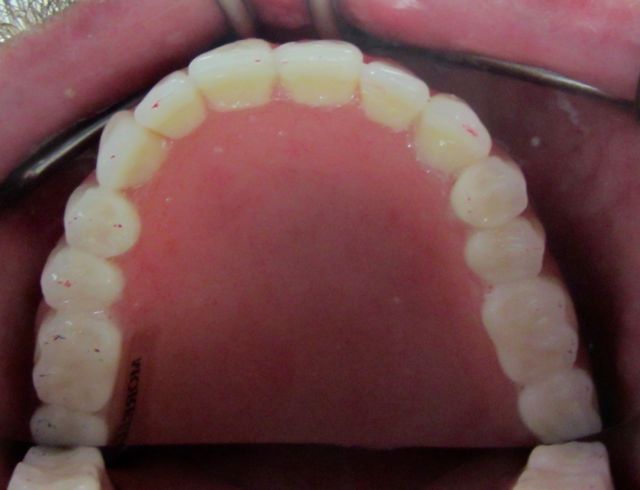

On the upper arch, we had Mike chew on articulating paper, to check on where his denture is chewing.